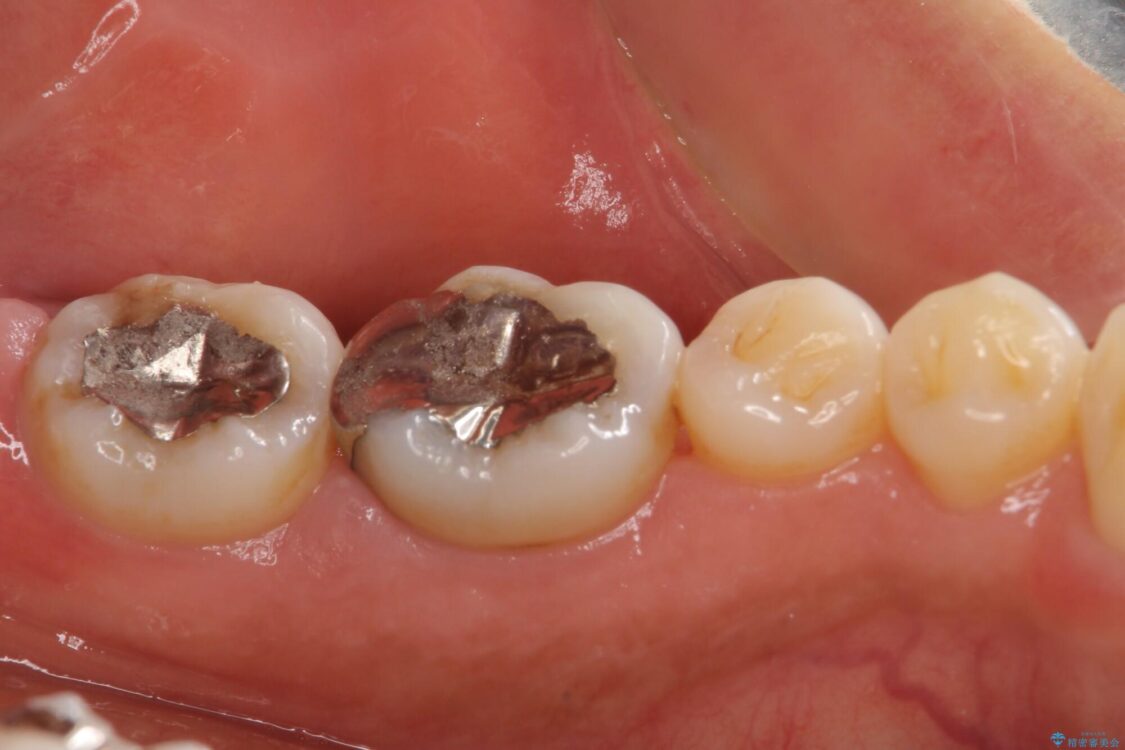

以前むし歯治療をした後から定期的に痛むことがあるとのことで、レントゲン写真より神経組織が失活していることが予想されました。

銀歯を外すと神経組織の一部が取り除かれており、歯根に付け根に穴が空けられている状態でした。

出血の原因は以前の治療で空けられた穴であると考え、封鎖をするとともに根管治療を行い、その後オールセラミッククラウンにて補綴治療を行うこととしました。

治療途中